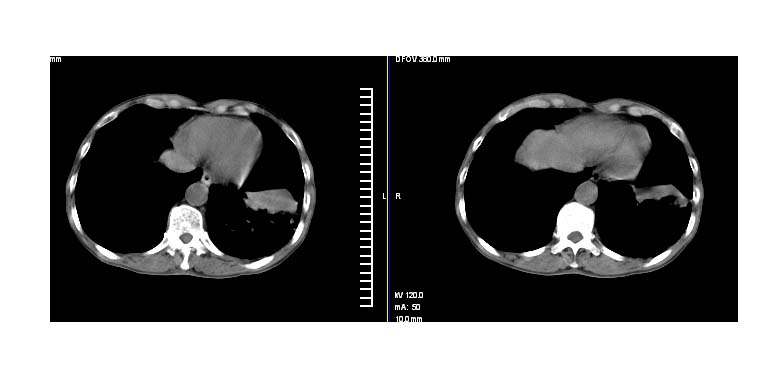

标题: CT11019:男性,66岁。发烧5-6天。治疗后无明显好转。 [打印本页]

标题: CT11019:男性,66岁。发烧5-6天。治疗后无明显好转。

左下肺中央型肺癌伴阻塞性肺炎\\肺不张可能性大,建议支纤镜检查.

1.左肺门似可见一小块影,由此考虑中央型肺ca并阻塞性肺炎改变;

2.左下叶背段肺tb(干酪性肺炎)?

3.单纯肺感染?建议进一步检查。

左下肺中心性肺癌伴下肺不张及周围阻塞性炎症

左下肺中央型肺癌伴阻塞性肺炎\\肺不张可能性大,建议支纤镜检查

左肺门下分增大见有结节影,基底干及分支显示不清,下叶体积缩小,呈片带状机磨玻璃样影显示。支持考虑左下肺中心型肺癌伴阻塞性肺炎及部分肺不张。建议纤支镜检查